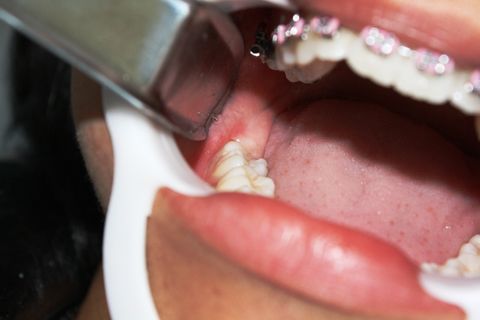

Paciente AB, sexo feminino, 19 anos, com indicação para exodontia dos elementos 18 e 48 incluso e mesio-incliniado.